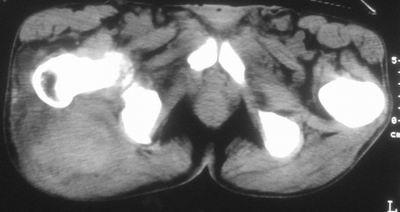

患者,男,63岁,自诉3个月前发现右臀部包块,触及疼痛,治疗后缩小。前天突然增大。无高热病史。

考虑-----右臀大肌,臀中肌---感染性病变可能性大。

病灶内部可见出血,首先考虑急性出血性病变.血肿?

给个骨窗,判断一下肿块是否与髂骨有关,肿块内出血是肯定的,至于是感染形成的脓肿还是起源于肌肉或纤维组织的肉瘤则难以确定,不过从影像上看,包膜完整,且环形增厚,病灶下部见斑片状底密度坏死,个人倾向感染可能性大

肌间隙明显混浊,三个月前治疗有缩小,支持考虑臀大肌下脓肿伴出血,肿瘤如果出现瘤内出血的话瘤外边界应该较清楚,现在表现为一种恶性征像,但骨质无明显异常,且臀小肌边界清楚,不符合恶性表现.